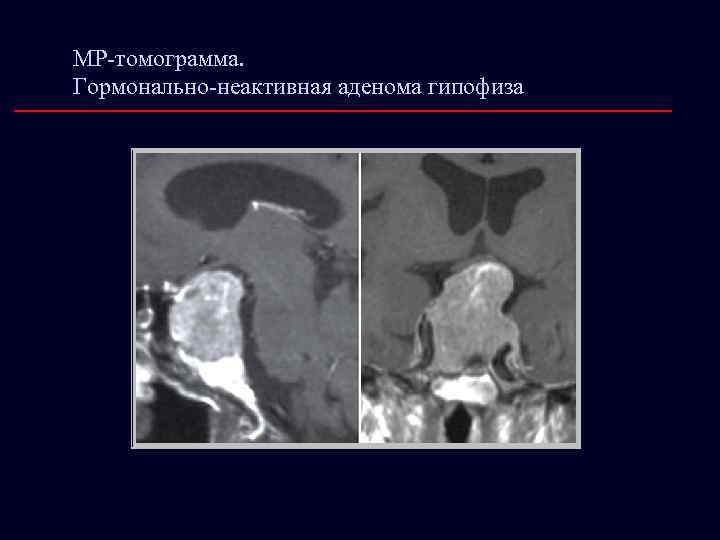

МР-томограмма. Гормонально-неактивная аденома гипофиза